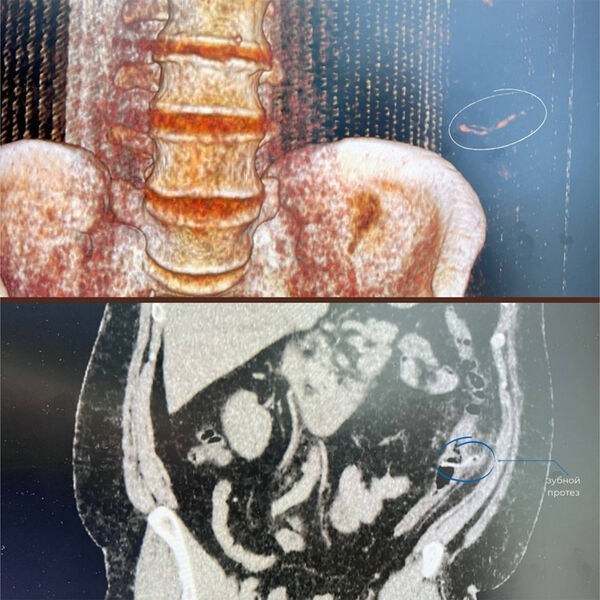

Врачи Нижневартовской окружной клинической больницы помогли пациенту с зубным протезом в кишечнике. Об этом сообщили в пресс-службе медицинского учреждения.

Пациент обратился к врачам с жалобами на боль в кишечнике и повышенную температуру тела. Мужчина рассказал, что за два дня до визита в больницу он случайно проглотил зубной мост.

Обследование показало, что протез из-за своей формы зацепился за стенку кишечника и вызвал воспаление. Не обнаружив у мужчины прободения кишечника, врачи приняли решение об удалении инородного предмета эндоскопическим путем.

«Сначала мы исключили возможную перфорацию кишечника, а затем приступили к операции: завели колоноскоп, осмотрели нужный участок кишки, «дошли» до зубного протеза, накинули на него эндоскопическую петлю и осторожно извлекли», — поделился врач больницы Ахмад Джабборов.

Через шесть дней после операции пациента выписали из стационара.